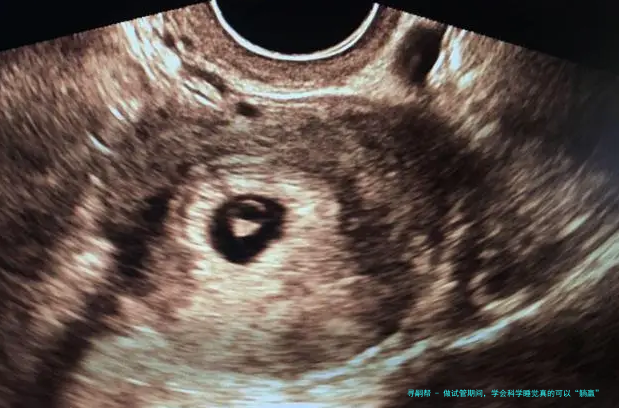

⑴在促排卵期间,可以适当多休息,但是预防长时间坐、久卧等情况,影响到身体健康和促排卵效果。促排卵用药后,女性的卵巢内多颗基础卵泡的发育,以及内里激素水平发生变化,此时女性可能会有萎顿感,可分频繁短暂时间地坐卧休憩,但是应注意掌控时间,并且按时用饭和如厕。按时睡醒活动身体,不仅有益于身体血液的反复,还可改善胃口,提高卵巢对促排用药的反响,从而提高获卵数目和素养。于采卵术后要躺床休息6—8小时,随后就可以痊愈正常的生活,纪律作息、做好卫生管理防备创口感染、避免身体疲劳和激烈运动就可以。

二、胚胎移植后。从医院抵家休息,要严密按医嘱躺床休憩满48小时,因为这个时间是囊胚移植后游离寻找俱佳着床位置的时间段,充分在床上休憩的要求是准妈妈除了正常的吃饭和如厕外,都须要十足卧床休息,在床上姿势可以是平卧、侧躺或斜卧,注意斜卧的姿势要小于四十五度。如厕时要抉择坐便的方式,避免深蹲、身体动作幅度大而影响到囊胚的游离,防备异位妊娠或滑胎的出现。48小时之后,就能正常生活和事业了,防止久卧对身体血液、心理压力、睡眠、身体代谢和排毒素等方面的影响,反而不利于胚胎的着床和胎儿健康发育。尚有少许,便是维系轻快愉悦的心态,相信并对试管婴儿抱有等待,如此结果就可以正向发展了。